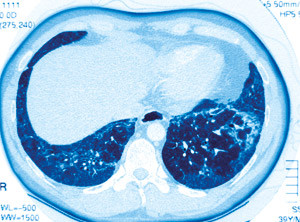

– Andelen bilaterale lungetransplantasjoner er økende også i Norge, og det samme gjelder langtidsoverlevelsen, sier overlege Øystein Bjørtuft ved Lungemedisinsk avdeling, Oslo universitetssykehus, Rikshospitalet. – Denne undersøkelsen gir ny kunnskap om premissene for valget mellom bilateral og unilateral transplantasjon.

Pasienter med idiopatisk lungefibrose, dvs. fibroserende alveolitt, har ofte liten nytte av medisinsk behandling, og dødeligheten er høy. Disse bør derfor henvises og lungetransplanteres tidligere i sykdomsforløpet. Donortilgangen er imidlertid begrenset, noe som bidrar til vanskelige medisinske og etiske vurderinger, sier Bjørtuft.